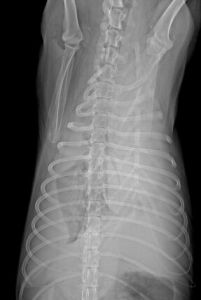

當胸導管受壓或堵塞時,管內壓力增高致導管或其在縱隔內分支破裂乳糜液反流、溢出而進入縱隔,繼之穿破縱隔進入胸腔,形成乳糜性胸腔積液也有可能因胸導管壓力高,發生肺內及肋間淋巴管的擴張反流,乳糜液不經縱隔而直接漏入胸腔由於解剖上的原因,阻塞或壓迫發生在第五胸椎以下時,僅出現右側乳糜胸,在第五胸椎以上時,則出現雙側乳糜胸。

進一步行放射性核素淋巴管顯像或X線淋巴管造影術,以觀察淋巴管阻塞及淋巴管外溢部位很有必要可行胸腹部CT檢查,了解胸導管沿途有無腫大淋巴結或其他腫物。這對確定病因是很必要的。